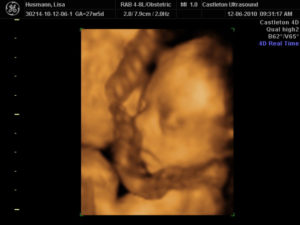

Для диагностики обвития пуповиной применяют ультразвуковое исследование. Оно помогает определить структуры плаценты, пронаблюдать положение канатика.

• При проведении УЗИ видны круговые петли пуповины на шейке ребенка

• ультразвуковое исследование, при котором возможно увидеть либо заподозрить обвитие пуповиной шеи или других частей плода, так как в некоторых случаях очень сложно отличить, находятся ли петли пуповины возле шеи плода или имеется обвитие: при данном исследовании мы не имеем возможности объемного изображения, позволяющего рассмотреть объект со всех сторон — например, заглянуть назад. Нужно отметить, что определить длину пуповины по данным УЗИ во время беременности не представляется возможным, так как пуповина как бы «свернута» в тесном пространстве между тельцем малыша и стенкой матки;

Обвитие пуповиной можно увидеть на экране компьютера при УЗИ

Фото помогут увидеть, как выглядит на снимке такой вид обвития пуповиной.